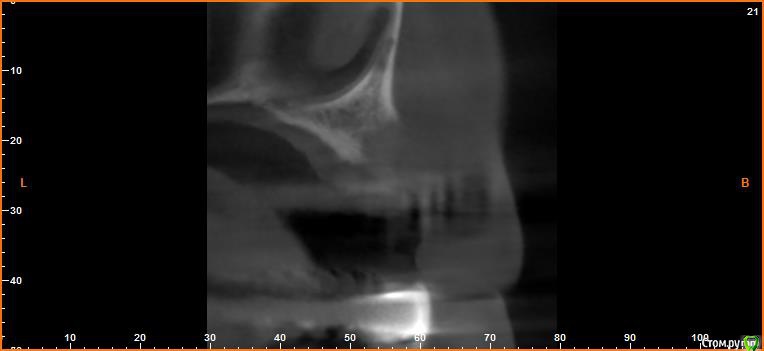

борисович Опубликовано 16 февраля, 2017 Автор Поделиться Опубликовано 16 февраля, 2017 Если сделать только синус получиться поставить импланты только в проекции 16,17 . В проекции 14,15 строение гайморовой пазухи узкое очень, вы думаете не стоит заниматься вертикалью? Спасибо за ответ Ссылка на комментарий